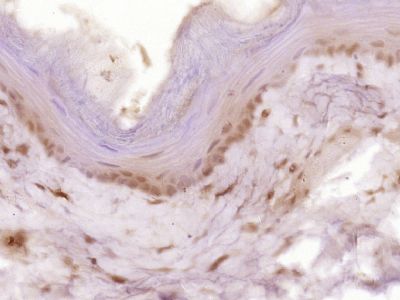

多聚甲醛固定,石蜡包埋(小鼠小肠);用柠檬酸钠缓冲液(pH6.0)煮沸15min后提取抗原;用3%过氧化氢阻断内源性过氧化物酶20分钟;阻断缓冲液(正常山羊血清)37℃30min;用细胞周期蛋白B1进行抗体孵育多克隆抗体,未结合(BS-057 2R)1:400在4℃过夜,然后按照SP试剂盒(兔)(SP-023)指导和DAB染色进行操作。多聚甲醛固定,石蜡包埋(大鼠食管);用柠檬酸钠缓冲液(pH6.0)煮沸15min后获得抗原;用3%过氧化氢阻断内源过氧化物酶20分钟;阻断缓冲液(正常山羊血清)37℃30min;用(cyclin B1)聚体抗体孵育。Lon抗体,未结合(BS-057 2R)1:400在4℃过夜,然后按照SP试剂盒(兔)(SP-023)指导和DAB染色进行操作。组织/细胞:小鼠胚胎组织;4%多聚甲醛固定和石蜡包埋;

抗原提取:柠檬酸缓冲液(0.01M,pH 6),15min煮沸,用3%过氧化氢阻断内源性过氧化物酶30min;37℃下阻断缓冲液(正常山羊血清,C-00 05)20 min;

孵育:抗Cyclin B1多克隆抗体,未结合(BS-057 2R)1:500,在4°C过夜,随后与二级抗体(SP-023)和DAB(C-00)染色结合。